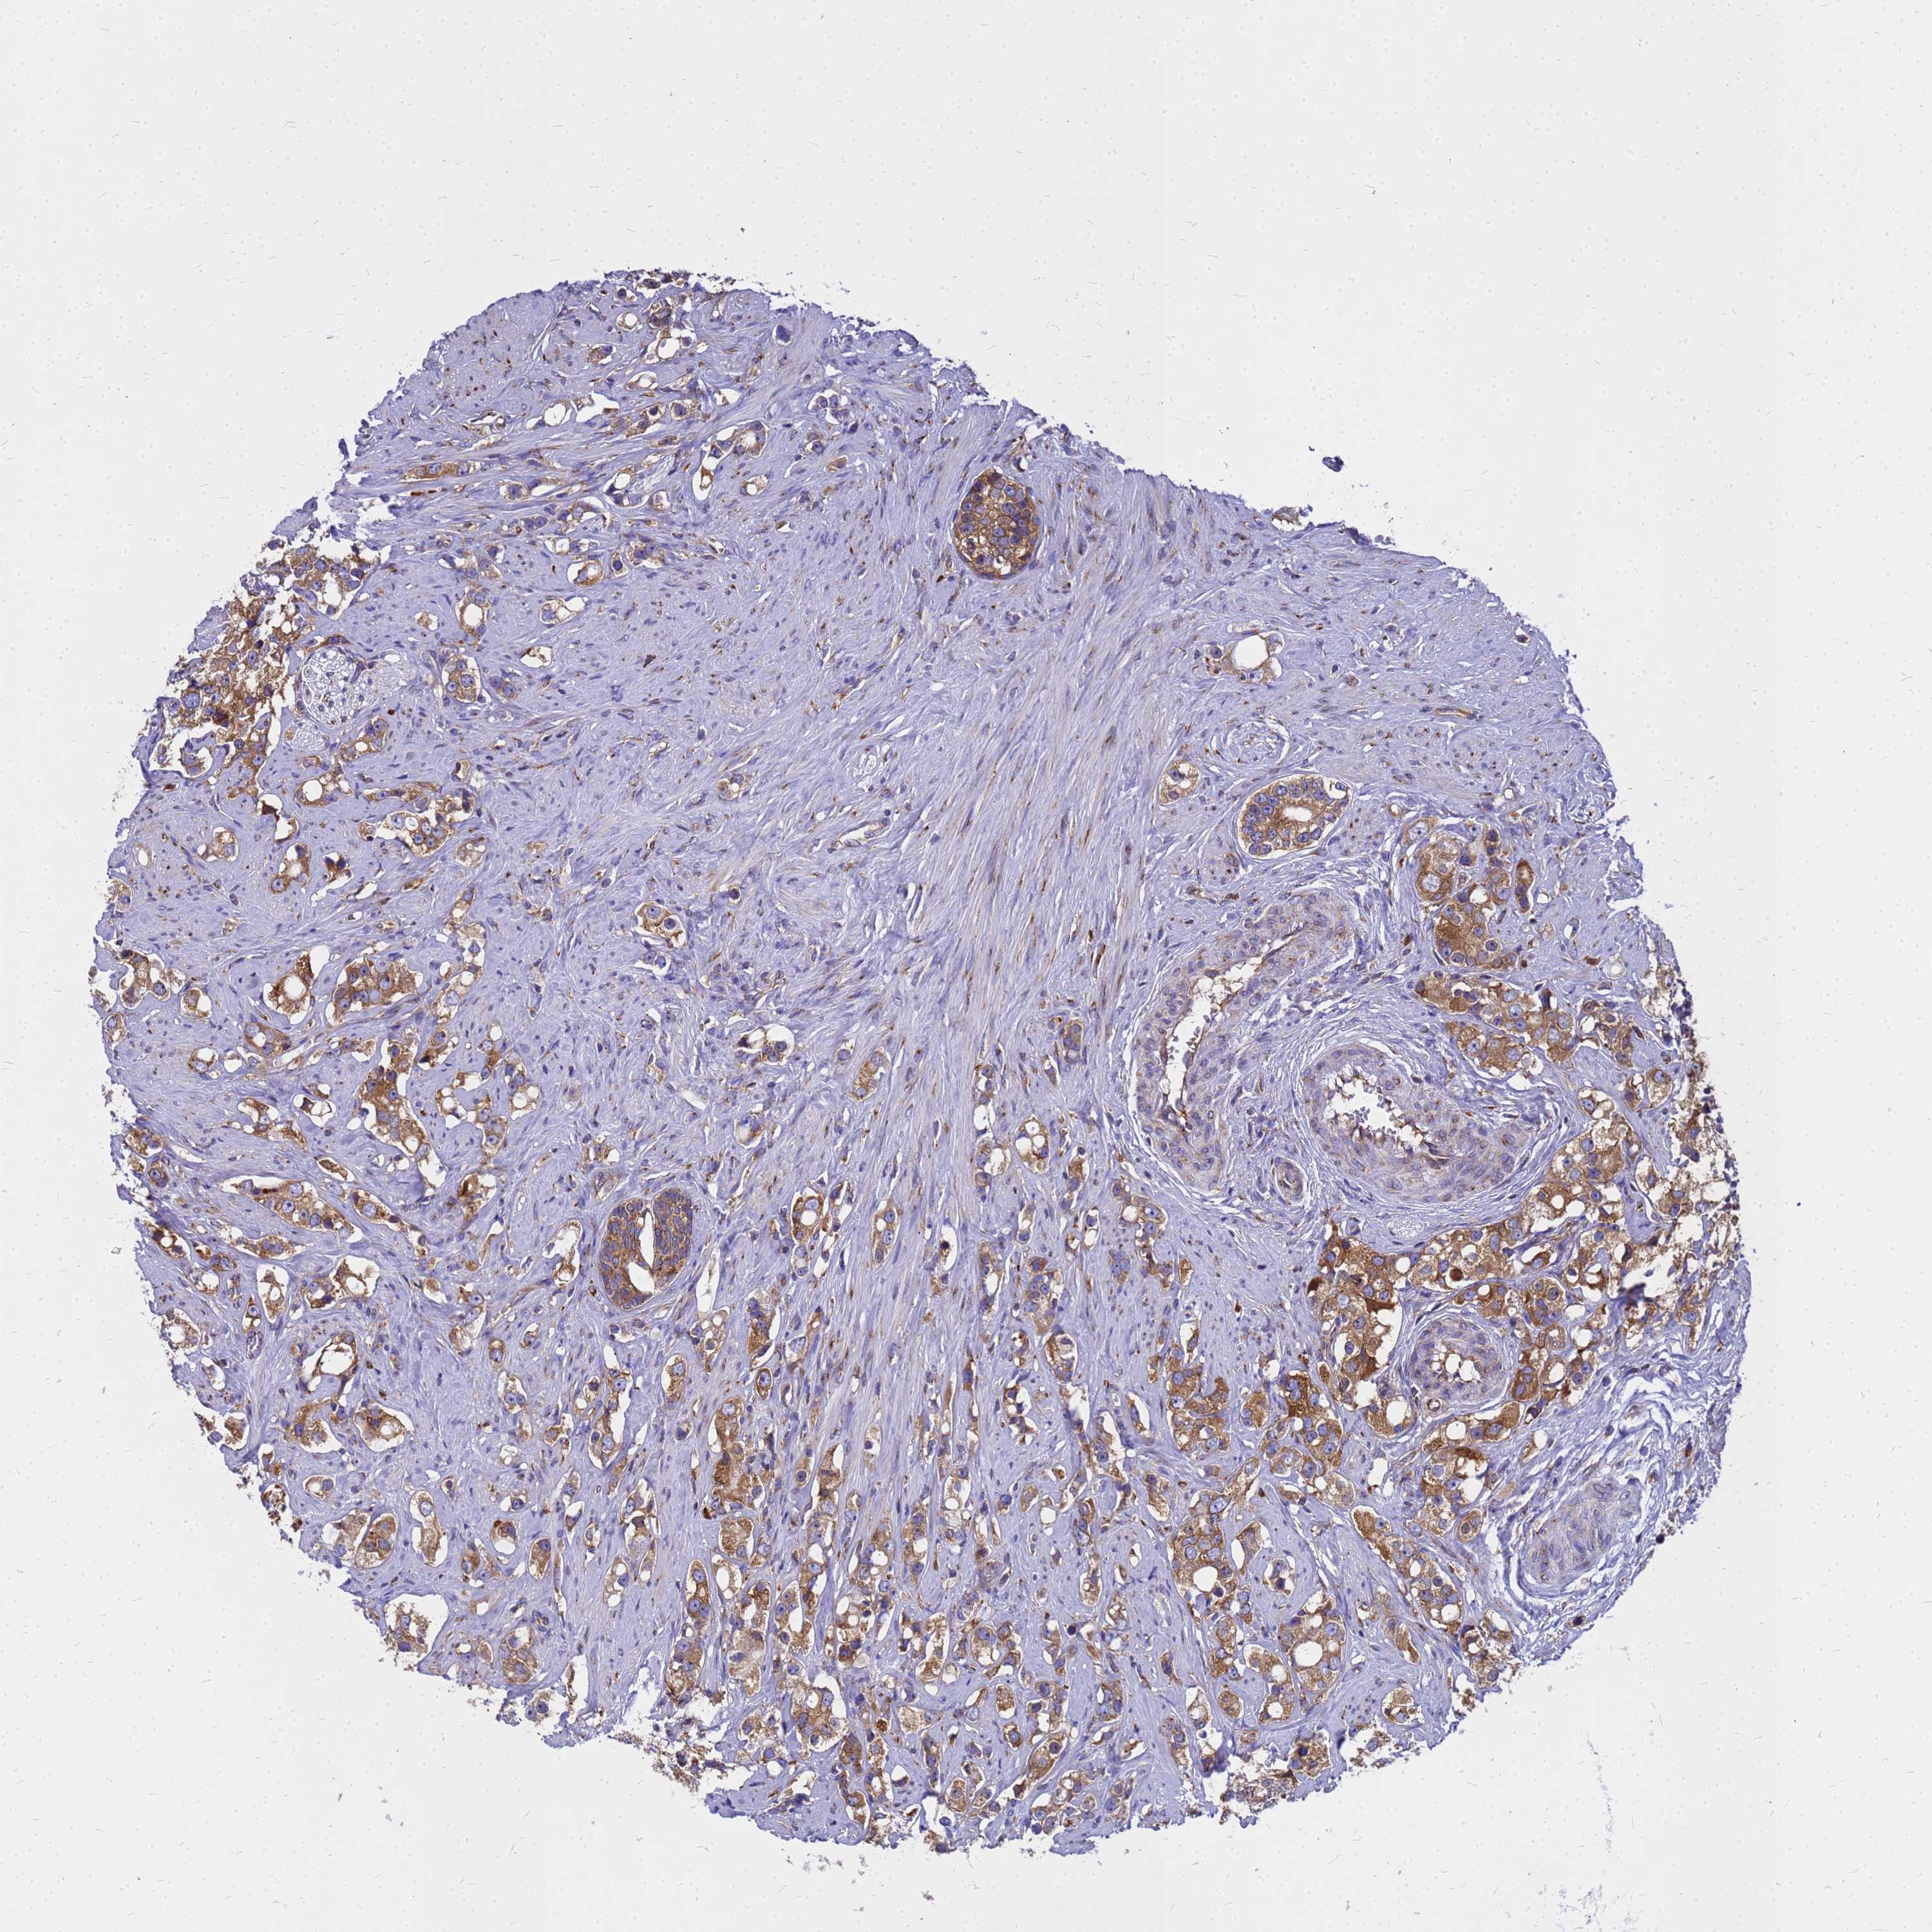

PROSTATE CANCER - Protein expressioni

A mouse-over function shows sample information and annotation data. Click on an image to view it in a full screen mode. Samples can be filtered based on level of antibody staining by selecting one or several of the following categories: high, medium, low and not detected. The assay and annotation is described here.

Note that samples used for immunohistochemistry by the Human Protein Atlas do not correspond to samples in the TCGA dataset.

Antibody stainingi

Antibody staining in the annotated cell types in the current human tissue is reported as not detected, low, medium, or high, based on conventional immunohistochemistry profiling in selected tissues. This score is based on the combination of the staining intensity and fraction of stained cells.

Each image is clickable and will lead to virtual microscopy that enables deeper exploration of all samples and also displays staining intensity scores, fraction scores and subcellular localization as well as patient and tissue information for each sample.

Antibody HPA045101

Staining

High

Medium

Low

Not detected

Intensity

Strong

Moderate

Weak

Negative

Quantity

>75%

75%-25%

<25%

None

Location

Nuclear

Cytoplasmic/membranous

Cytoplasmic/membranous,nuclear

Adenocarcinoma, NOS

Adenocarcinoma, High grade

Adenocarcinoma, Low grade